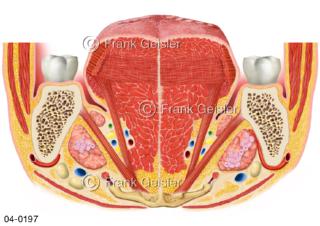

Bildergalerie Topografie Organe

Bilder zur topografischen Anatomie, die Lage der Organe und die Strukturen nach ihren räumlichen Lagebeziehungen zueinander, Übersicht der inneren Organe im Kopf und im Rumpf, Topografie der Organe im Brustraum (Thorax) und im Bauchraum (Abdomen)